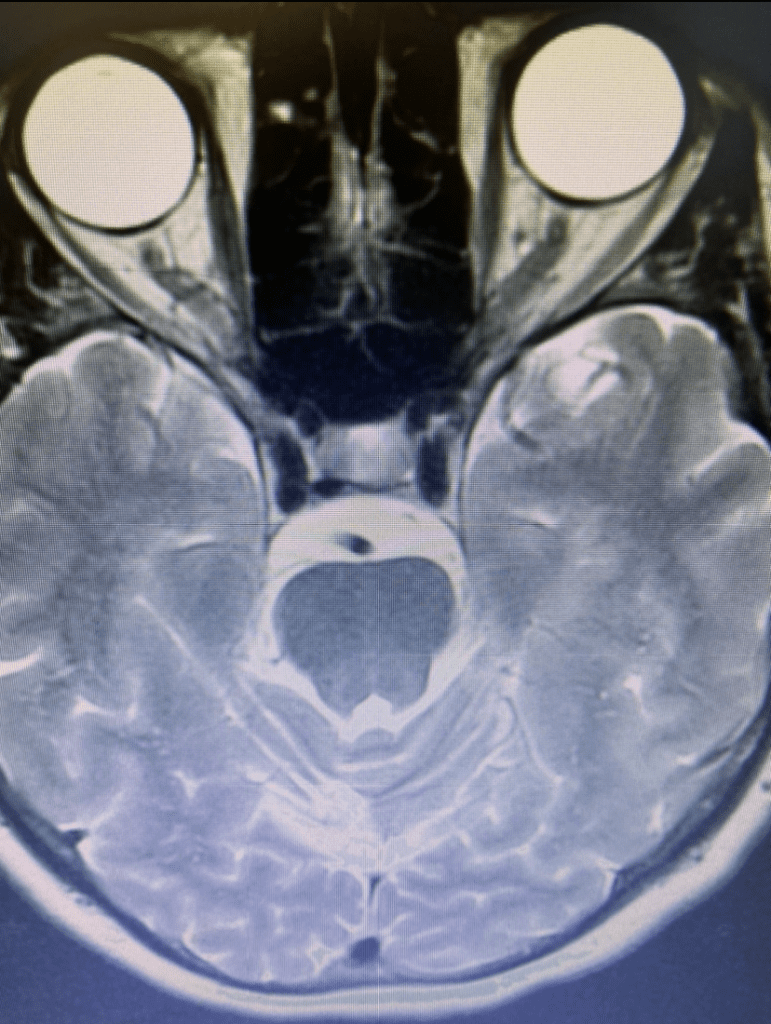

Subsequent to this, she underwent Gamma Knife treatment of the cerebellar AVM (figure 1) with Dr. Michael Brisman. She had no subsequent problems. Subsequent imaging showed that the AVM was starting to thrombose. She was then lost to follow up for many years.

Figure 1. Axial MRI with contrast at the time of gamma knife treatment showing the tightly conformal 50% Isodose line contoured around the AVM of the posterior superior cerebellar vermis.